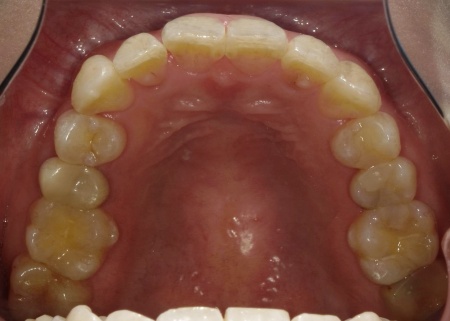

拝見したところ、叢生(そうせい)が上下前歯に確認できました。

今回のケースでは上前歯にやや目立つ重なりがあり、下前歯は軽度の叢生が見られました。

叢生は見た目の問題だけでなく、歯と歯の間に歯ブラシが届きにくくなるため汚れが残りやすく、虫歯や歯周病のリスクが高くなる可能性があります。